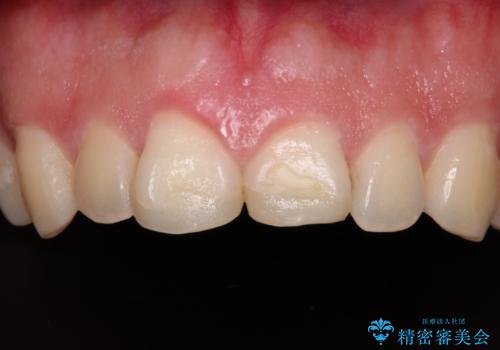

- 競技用自転車を運転中に転倒して前歯を強くぶつけ、欠けてしまったとのことで来院された患者様です。

近医にて欠けて部分を樹脂で修復してもらったものの、舌での感触が悪く、しみる感覚があるため、オールセラミッククラウンによる補綴治療を希望されていました。